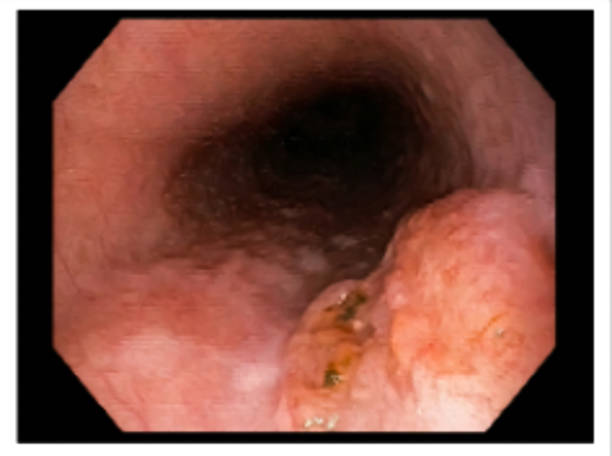

식도염

식도암 초기 증상 중 하나로서, 식도내에 염증이 발생하는 것을 의미합니다. 식도암은 식도내 세포들이 비정상적으로 성장하면서 발생하는데, 이 과정에서 염증이 발생할 수 있습니다. 식도염은 식도암과는 직접적인 관련은 없으나, 만약 지속적으로 발생하면 식도암 발생 위험이 증가할 수 있습니다. 식도염은 식도의 통증, 역류증상, 역류성 식도염 등의 증상을 유발할 수 있습니다.